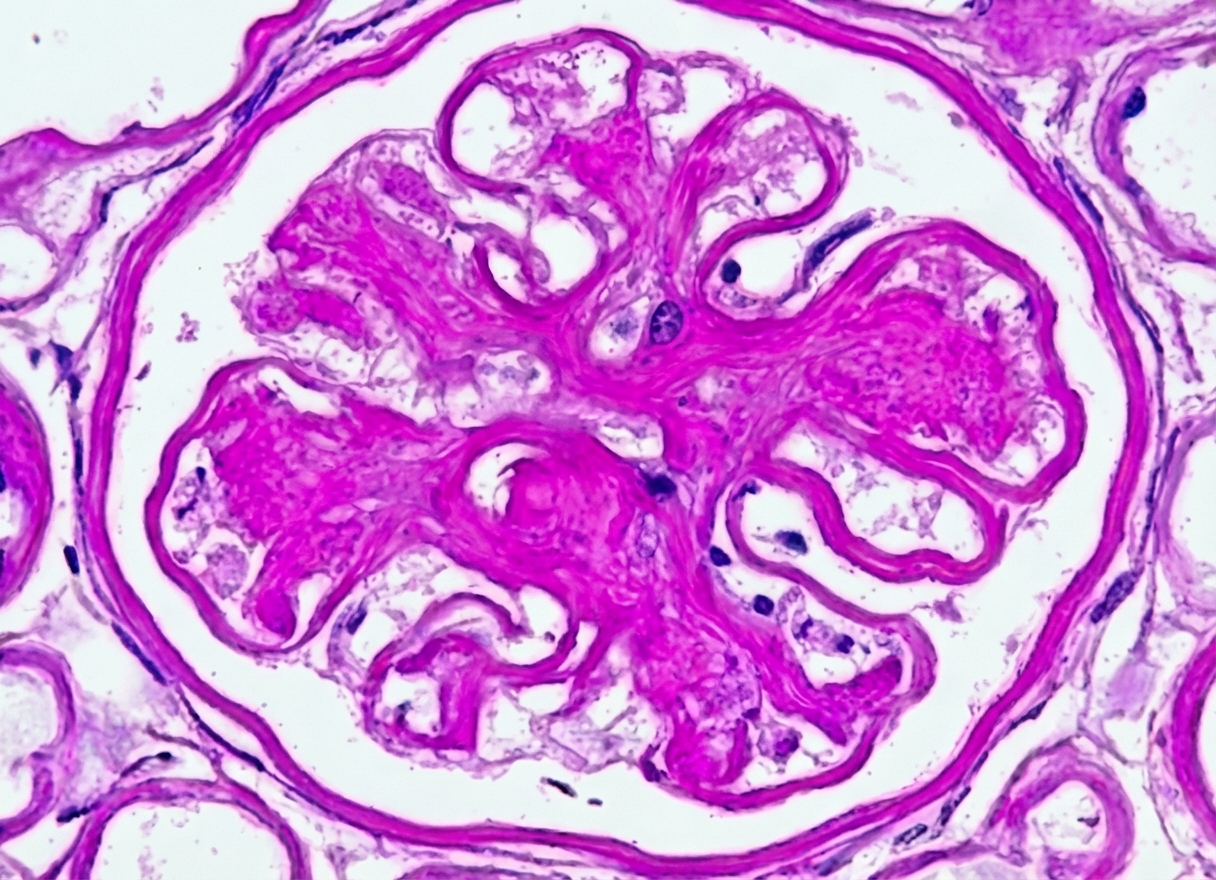

fibrosiskidney

Clinical TranslationFibrosis Model

UUO Mouse Model

Species: Mouse

Duration: